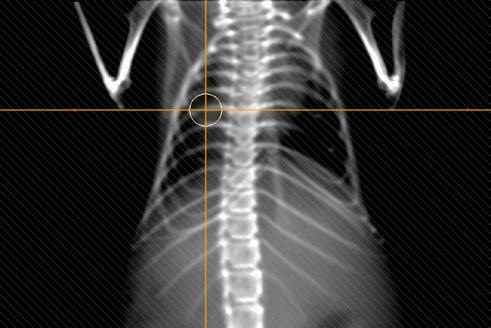

Figure 7. A digitally reconstructed radiograph for one of the beams on Figure 4.